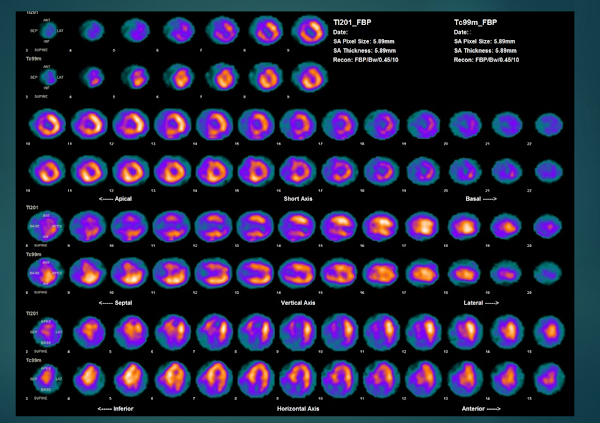

- 医療現場でもKYT(危険予知トレーニング)で医療事故を未然に防ぐ取り組みがなされている